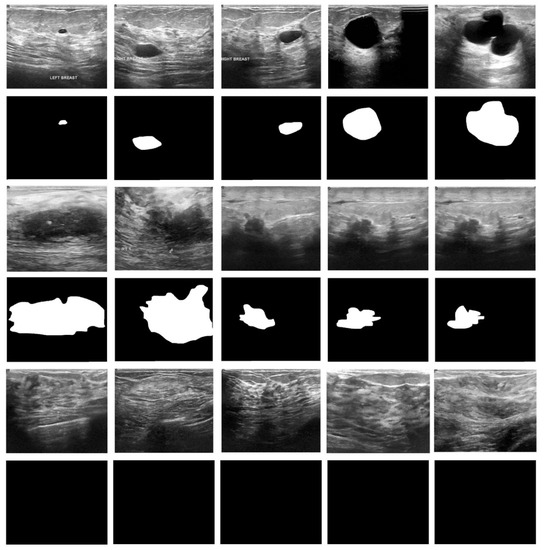

The proposed model was implemented on a PC with the following configuration: Intel i5, 8th generation PC with 16GB RAM, MSI L370 Apro, and Nividia 1050 Ti4 GB. The researchers used Python 3.6.5 along with pandas, sklearn, Keras, Matplotlib, TensorFlow, opencv, Pillow, seaborn and pycm. The experimental analysis was conducted for the EDLCDS-BCDC technique using the benchmark Breast Ultrasound Dataset [24], which comprises 133 images classified as normal, 437 images classified as benign, and 210 images classified as malignant. The dataset holds 780 images sized in the range of 500 × 500 pixels. Figure 3 shows the input images along with ground truth images. The first, third, and fifth rows represent the original mammogram images. Next, the respective ground truth images are given in the consecutive second, fourth, and sixth images. Furthermore, Figure 4 includes a histogram of the images (for the input images given in the first, third, and fifth rows in Figure 3).

Figure 3. Sample and ground truth images (benign/malignant/normal).